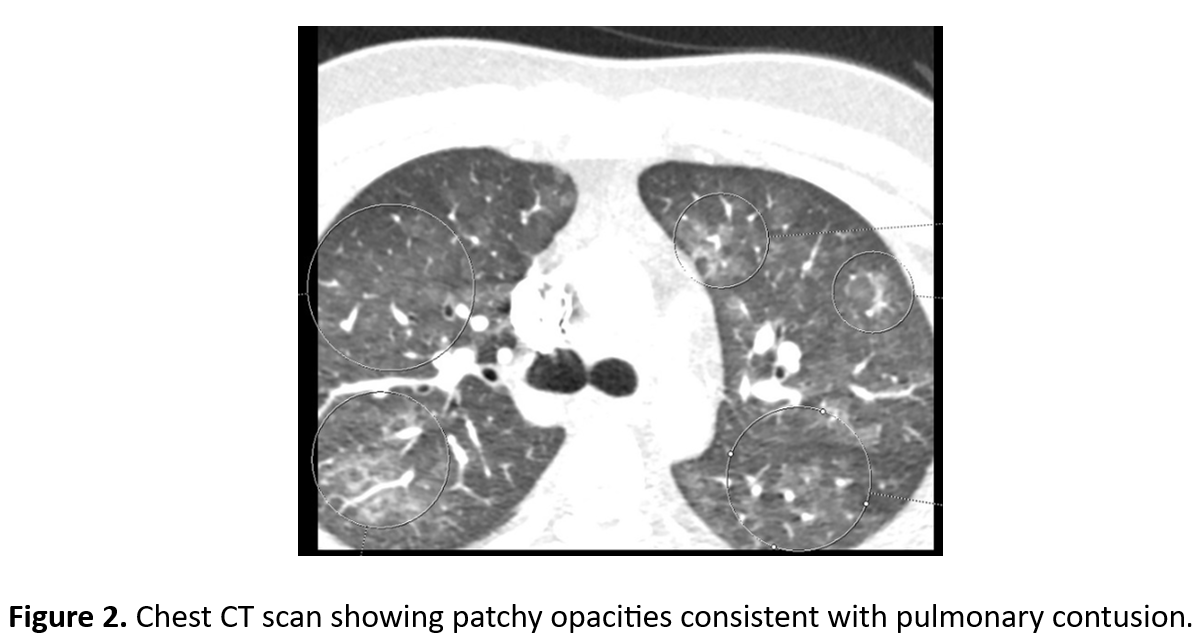

Relevant Test Results Prior to Catheterization

STEMI was initially unrecognized, and no ECG was performed for over 24 hours. As symptoms worsened, ECG showed anterior STEMI and Troponin I was elevated. Echo revealed LVEF 45% with akinetic mid–apical LV segments. Due to respiratory distress, myocarditis or contusion was suspected. Cardiac CT confirmed total LAD occlusion. The patient received Fondaparinux, aspirin 300 mg, and clopidogrel 300 mg before PPCI.